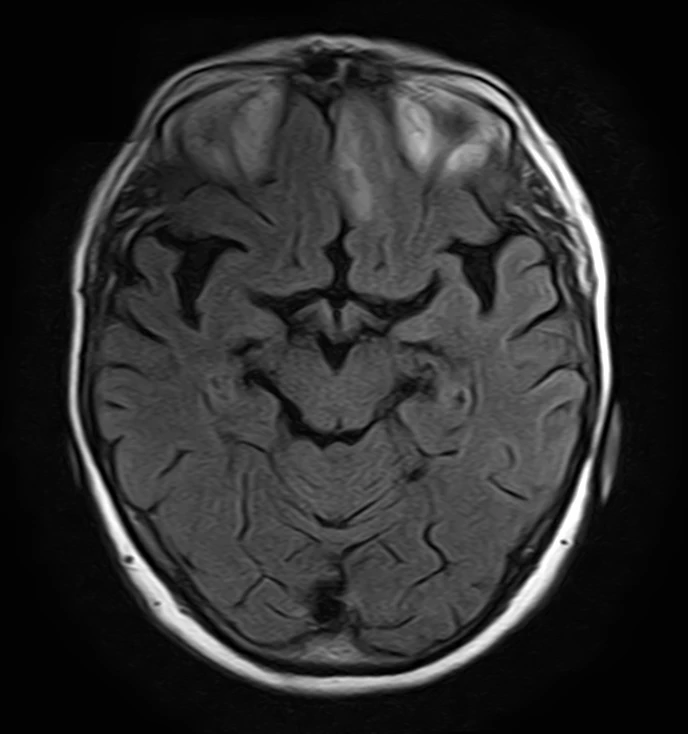

Вот, ещё один случай, все прекрасно, как мы с вами любим: диагноз по одному срезу. Рассеянный склероз. выполненны критерии диссеминации в пространстве. Есть очаг под наметом мозжечка, в мосту, кроме того, у него и морфология характерная для рассеянного склероза: субпиальный и вытянутый. И есть очаг рядом с корой, который её касается, по-умному – юкстакортикальный. Ну и ещё один юкстакортикальный

для гарантии 😅